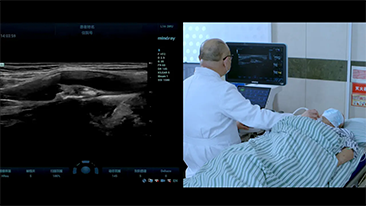

Mit den allgemeinen Bildgebungsl?sungen der Resona-Serie von Mindray k?nnen Arzt und ?rztin genauer und effizienter diagnostizieren sowie bessere Behandlungserfolge erzielen, durch umfassende geteilte Anwendung der Sonden und effiziente klinische Anwendungstools.

Das medizinische Umfeld ist komplexer geworden, die Zahl der schwierigen F?lle und Workloads gestiegen.